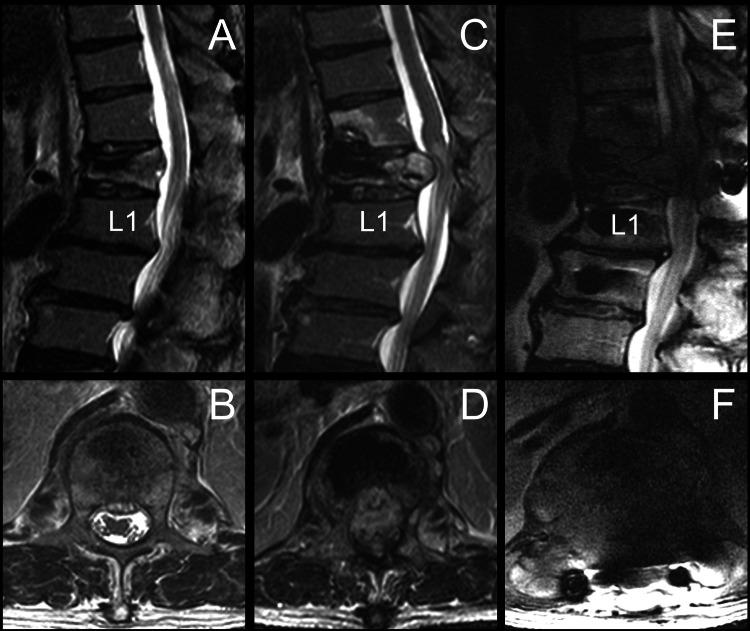

While osteoporosis is the primary cause of vertebral compression fractures (VCFs), it's crucial to promptly recognize pathological fractures through comprehensive diagnostic tests, including vertebral biopsies, to determine the exact etiology. For instance, a 66-year-old male with osteoporosis experienced worsening lower limb weakness and back pain after an initial vertebroplasty for a T12 compression fracture. Subsequent MRI revealed severe circumferential extradural compression at T12, leading to further surgeries that eventually uncovered metastatic adenocarcinoma from a pancreatic tumor. This case highlights the importance of precise diagnosis through vertebral biopsy and the necessity of sufficient ventral decompression or corpectomy, coupled with extensive laminectomy, to address severe neurological impairments like paraplegia. Prompt and accurate interventions can significantly improve patient outcomes and quality of life.

摘要

虽然骨质疏松症是椎体压缩性骨折(VCF)的主要原因,但通过包括椎体活检在内的全面诊断测试及时识别病理性骨折以确定确切病因至关重要。例如,一名患有骨质疏松症的66岁男性在接受T12压缩性骨折的初次椎体成形术后,下肢无力和背痛加重。随后的MRI显示T12水平存在严重的环形硬膜外压迫,导致进一步手术,最终发现是胰腺肿瘤转移所致的腺癌。该病例强调了通过椎体活检进行精确诊断的重要性,以及为解决诸如截瘫等严重神经功能障碍而进行充分的前路减压或椎体切除并结合广泛椎板切除术的必要性。及时准确的干预措施可显著改善患者的预后和生活质量。